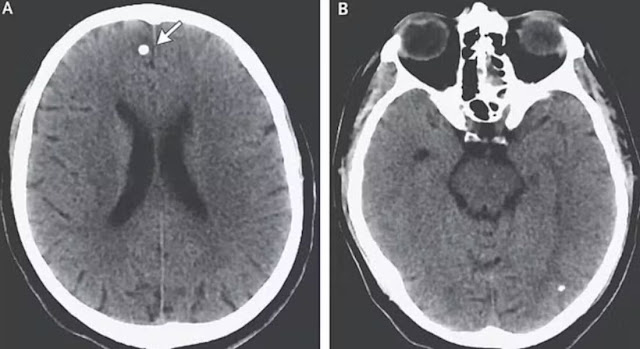

Após exames, os médicos descobriram que os parasitas haviam migrado para o cérebro, provocando cistos e inflamação. O tratamento envolveu medicamentos para matar os vermes e esteroides para reduzir a pressão no cérebro. Após semanas de internação, TE se recuperou e passou a emagrecer de forma saudável.